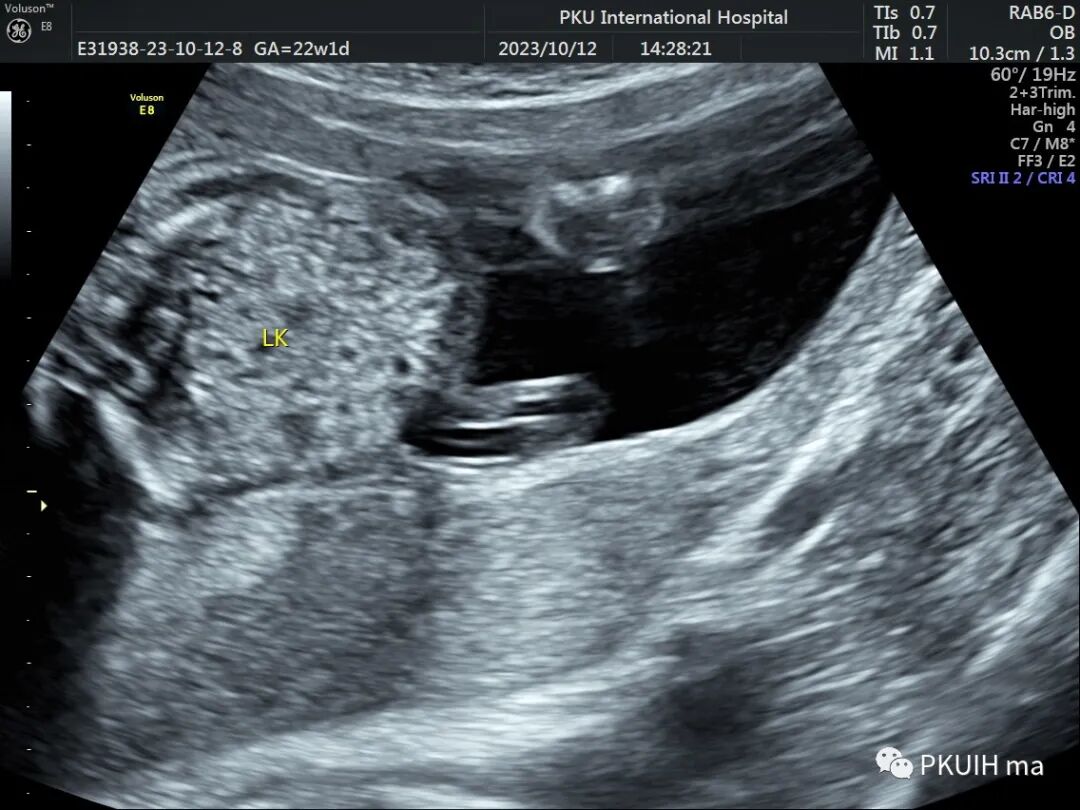

右肾大小位置正常,右肾动脉可见,左肾动脉缺如,正常的左肾区未见肾组织回声,可见肾上腺平卧。于膀胱后上方见一肾组织回声,大小约1.5x1.4x1.0cm,皮髓质分界欠清晰,血供来源于髂动脉。

肾缺如在成人和胎儿中经常能碰到并不是什么稀奇的事情,有的是先天未发育,有的是后天肾萎缩。正常人一个肾就够用,发现一侧肾缺如并不用担心,如果不合并其他异常也不建议引产。在日常检查中如果发现一侧肾区未见肾脏结构,此时不要着急下结论,要多扫扫其它区域,比如盆腔、胸腔。异位肾多发生于盆腔,容易合并肾发育不良。

异位肾较常见,发生率约1/1200,目前产前确诊并不困难。异位肾最常见的就是盆腔异位肾,占异位肾的一半以上,往往合并发育不良。血供可来源于腹主动脉或髂动脉,部分可有血管迷走。超声诊断标准:1、一侧肾区内未见肾组织回声;2、同侧的肾上腺呈平卧征;3、对侧肾可增大也可正常;4、盆腔可见一发育不良或发育正常的肾脏回声;5、可合并其他畸形,比如输卵管发育畸形或者是Vacterl综合征。